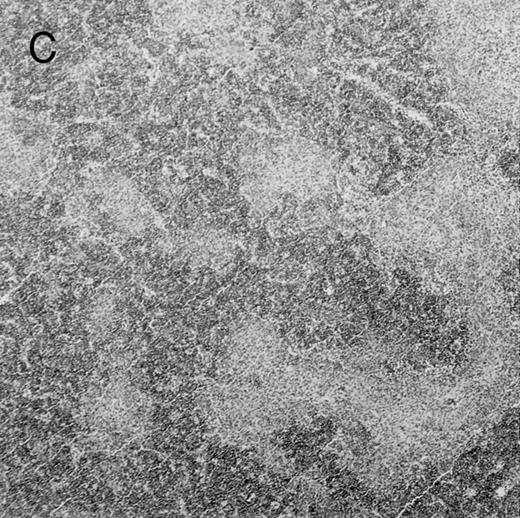

(C) B6 mice receiving FVB BM plus EpΔTK T cells and treated with GCV. (D) B6 mice receiving FVB BM plus EpΔTK T cells, treated with GCV, and developing a late onset GVHD (day 54).

Protection from GVHD was slightly less efficient in the group receiving EpΔTK CD3+ T cells. The survival rate was 79% at day 60 and 67% at day 120 (Fig 2B). However, two different outcomes must be distinguished. On the one hand, a majority of mice behaved as GCV-treated animals receiving EpTK T cells. They were apparently healthy, presented no skin lesions during a 120-day observation period, and showed complete donor-type hematologic reconstitution. There were no histological signs of GVHD in the spleen or liver (Fig 4C).